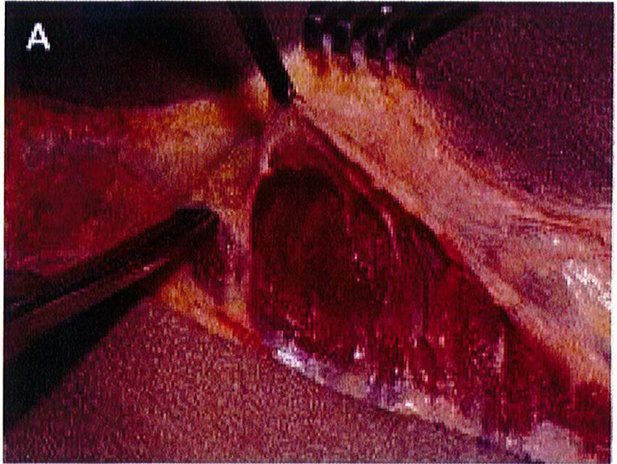

Hình. 3. (A) Lớp cân mạc che phủ cơ mông lớn. (B) Bóc tách lớp cân và cơ để tạo mặt phẳng cấy ghép. (Trích từ de la Pena JA, Rubio OV, Cano JP, et al. Subfascial Nâng mông. Clin Plast Surg 2006;33:409; đã xin phép trước khi đăng tải.)

của chúng. Cân cơ mông lớn – nhõ đều đi cùng với chiều hướng của lớp cơ chúng che phủ. Nên nhớ hệ thống cân cơ này buộc phải bảo tồn tối đa trong bất kỳ phẫu thuật nâng mông thẩm mỹ nào. Và khối implant khi đặt ở vị trí dưới cân sẽ đảm bảo không ảnh hưởng tới bất kỳ cấu trúc mạch máu thần kinh sâu nào (Hình 3).

khu vực dưới cân, từ đó có thế bóc tách được lớp cân mạc nguyên vẹn (Hình 9). Các vách ngăn này chạy cùng chiều với các bó cơ mông mà chúng che phủ tương ứng, nên khi bóc tách trông chúng như đang tỏả ra như hình rẻ quạt.

Dụng cụ bóc tách hai đầu tù, hình tròn được sử dụng để phân tách mặt phẳng vô mạch đã được bộc lộ bằng cách tiêm dung dịch trước đó, nhằm bảo tồn tối đa vách và lớp cân mạc. Nên thực hiện bóc tách từ trong ra ngoài, từ trên xuống dưới với một dụng cụ banh có đèn sợi quang (Hình 10). Để tách các vách ngăn, sử dụng một cây bóc tách dài có một đầu nhọn hoặc kéo dài (Hình 11). Các nhánh động mạch mông trên, mông dưới và một số mạch nuôi cho vùng cân mạc được đốt điện. Hãy chắc chắn